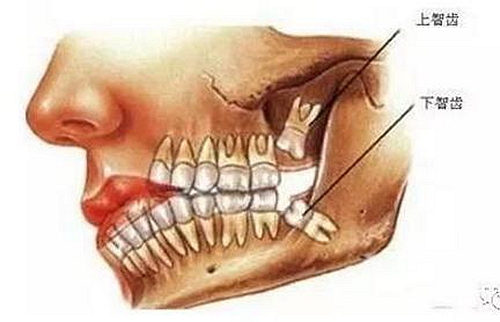

智齒也稱智慧齒、是人類的第三磨牙,隨著遺傳基因的不同智齒一般會在16-30歲之間長出,也是人一生中最后長出的牙齒,所以它最靠近喉嚨,因為此時期的人們心智比較成熟而得名。從門牙數(shù)往里第八顆,一般成年后長出來。由于人類進(jìn)化,這顆第三磨牙失去了作用。逐漸退化,限制于空間,有些長歪了,有些頂著前面的牙齒,有些埋伏在牙槽骨里出不來。

智齒周圍是牙槽骨,前面緊挨著第二磨牙,智齒下方大約兩三毫米遠(yuǎn)有一下頜神經(jīng)管,這神經(jīng)主要是下頜牙齒及下唇部位的知覺神經(jīng),一旦斷了,就會失去知覺。